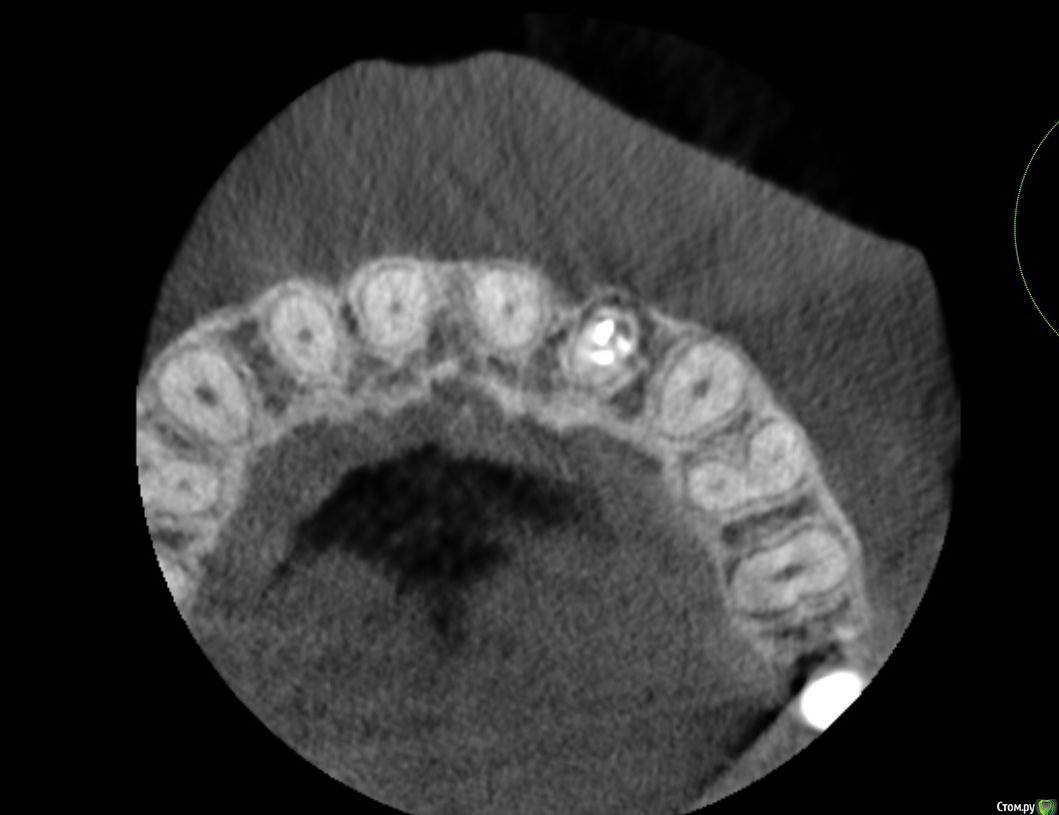

Lanasvlisa Опубликовано 21 апреля, 2017 Поделиться Опубликовано 21 апреля, 2017 Добрый вечер, уважаемые врачи! Вопрос по зубу 22, он леченый-перелеченный, сейчас на корне обнаружена киста, на десне над зубом свищевой ход. Какое ваше мнение: 1) удалять зуб и вместе с ним уйдет воспаление, прочищать все и заниматься имплантацией; или 2) можно каким-то образом удалить кисту, отсечь корень (читала о таком), но сам зуб не удалять? Если всё-таки 1), то можно ли осуществить в данном случае одномоментную имплантацию с нагрузкой? или можно одномоментную, но без нагрузки...? Спасибо огромное всем, кто посмотрит снимки и выразит свое экспертное мнение! С уважением, PS: прикрепляю скриншот из программы, но если этого недостаточно для определения диагноза и плана вмешательства, то скину ссылку на весь архив. Ссылка на комментарий

колесников Опубликовано 21 апреля, 2017 Поделиться Опубликовано 21 апреля, 2017 Резецировать там нечего,во время эндодонтического лечения произошла перфорация стенки корня зуба,вокруг этого участка очаг деструкции костной ткани. Это не лечится.По выставленной вами картинке объём деструкции не понятен. Решить возможность одномоментной имплантации и тем более немедленной нагрузки может только ваш лечащий доктор ,по результатам кт и в соответствии со своим опытом. Ссылка на комментарий